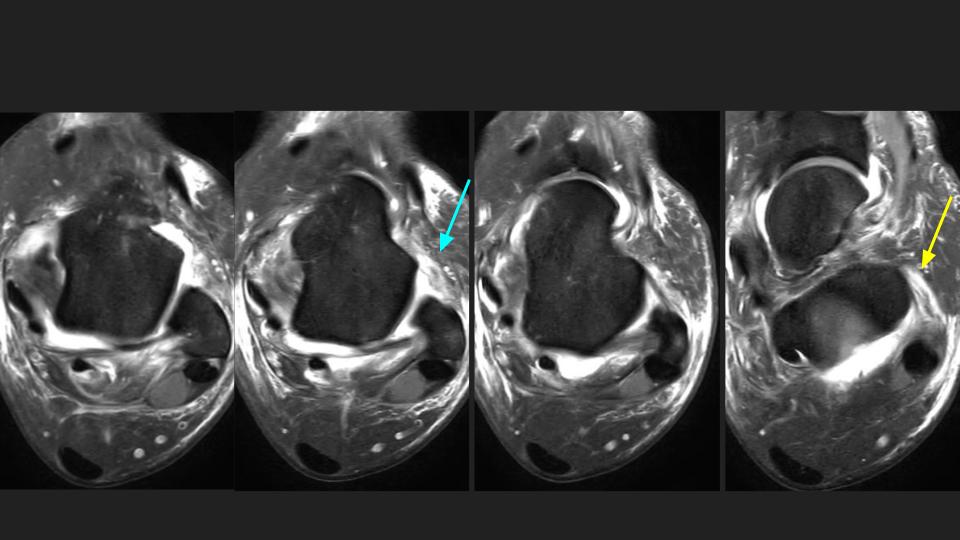

There is non displaced distal fibular shaft fx (see XR). There is a partial tear of the interosseous membrane (red arrows). There is complete AITFL rupture (white arrows). Gr I sprain of the PITFL and Laciniate ligaments. I think there is double band morphology of the ATFL, with a complete tear of one band and the other band intact (blue arrow). There is partial tear of the CFL (yellow arrow)...generally the CFL tears after the ATFL. The key point is that there should ALWAYS be overlap of the distal tibial and fibula in the Oblique or Mortise view...in this Obl view there is none. Syndesmotic Complex injury should have been suspected on the basis of the XR findings.